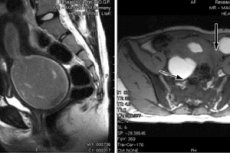

Самым важным механизмом установления правильного диагноза в случае аплазии влагалища является инструментальная диагностика. Использование зонда при осмотре позволяет выявить за девственной плевой влагалище, которое слепо заканчивается. При недостаточности таких мер для установления диагноза прибегают к лапароскопической диагностике. Это малоинвазивный хирургический метод исследования, который даёт возможность с помощью оптического лапароскопа через небольшие отверстия проникнуть в брюшную полость, и дать изображение репродуктивных органов в увеличенном размере на монитор. Безоперационные методы диагностики – ультразвуковое исследование (УЗИ) и магниторезонансная томография (МРТ) органов брюшной полости покажут, существуют ли дефекты других детородных или соседних с ними органов. Может не быть матки при нормальных яичниках и фаллопиевых трубах, а может быть недоразвитая, обнаружены дефекты мочевыводящей системы.